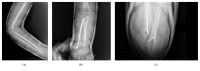

An Undescribed Monteggia Type 3 Equivalent Lesion: Lateral Dislocation of Radial Head with Both-Bone Forearm Fracture

Monteggia fractures are accepted as hard-to-recognize and easy-to-handle fractures. Adequate radiographic investigations and clinical examinations are necessities. This case holds unique features involving diagnosis and treatment. In this case, the radial head was dislocated laterally while both bones were fractured in the proximal diaphysis, being the first to be mentioned in the literature. Closed reduction of the ulna is the preferred method of handling and almost always results in reduction of the radial head. Literature obligates ulnar reduction as a preliminary to reduce and stabilize the radial head. Closed reduction reduced the ulna but the radial head was not reduced. Hence an intramedullary K-wire was used to reduce the radial head and a long arm cast was used to stabilize the reduction. The operation was successful and follow-up showed no complications.